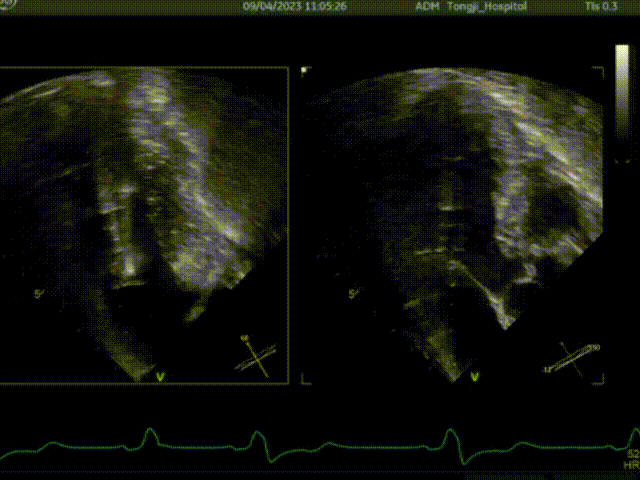

二、行经心尖介入二尖瓣夹合手术ValveClamp

ValveClamp抓捕瓣叶并收入闭合环内

该患者为老年女性,左室流出道压差134mmHg,二尖瓣前后叶冗长,即便切除了增厚的心肌组织,二尖瓣仍然可能存在反流,同时前叶冗长有阻挡流出道的风险,术前魏翔教授团队就治疗方案进行了充分的商议,最终提出使用两种来自中国原创的新器械(心肌旋切系统+ValveClamp),在同一切口下行不停跳魏氏心肌旋切术加经心尖介入二尖瓣夹合术。

肥厚型梗阻性心肌病是最常见的遗传性心血管疾病之一,全国约有200多万人罹患该病,起病隐匿,但病情会慢慢加重,一活动就容易导致胸痛胸闷,近年来发病率逐年升高,是青少年及运动员猝死的主要原因。目前该疾病的治疗方式主要有药物治疗、外科手术及化学消融等。传统的外科方式需要在心脏停跳、体外循环下进行手术,创伤大、手术风险高、恢复慢。目前全国每年开展肥厚型梗阻性心肌病的外科手术并不多,全球年手术量超过100例的中心不超过5家。肥厚型梗阻性心肌病合并重度二尖瓣反流的患者,切除肥厚的心肌组织后,有一部分患者的仍存在二尖瓣反流的问题。微创经心尖不停跳心肌切除手术+经心尖二尖瓣钳夹手术方式,可以有效解除患者二尖瓣反流及以及流出道受阻的问题,实现了“1+1大于2”的效果,这一方式大大降低了对患者的创伤,同时无需体外循环辅助,术后恢复快等优点。与此同时,应用Valveclamp经心尖介入二尖瓣夹合器系统具有操作简单、手术时间快,医生学习曲线短等优点。单纯超声引导下就可进行,无需医院配备复合手术室。